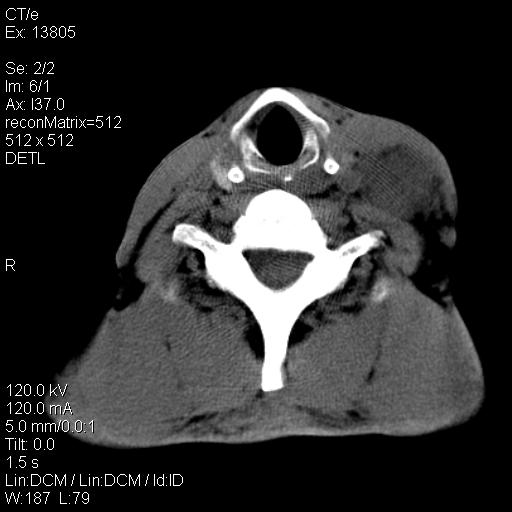

上腹部疼痛一月,呕吐10天,发现左侧颈部包快10天 胸部cr片未见明显异常。

左侧胸锁乳突肌下方、颈血管旁低密度肿块影,肿块密度尚均匀,边缘大部分清楚,邻近组织稍受压移位。考虑颈部神经鞘瘤可能性大。

颈部及腹膜后淋巴瘤可能性大